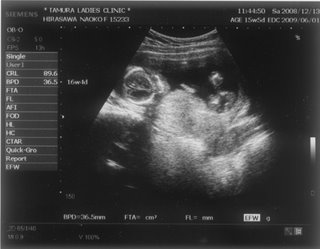

お腹の赤ちゃんは、今日で24週と4日。あっという間に7ヶ月突入です

![]() お腹もドンドン、食欲もドンドン出ていてあしたの4回目の検診コワーイ ![]() 妊娠発覚から三ヶ月半、なのにもう妊娠7ヶ月!頭がついていきません ![]() でも、毎日激しくなる胎動に感激している日々です ![]() 一回目の検診から4週後、2度目の検診に行ってきました。 2008年12月13日 赤ちゃんは15週と5日 ![]() 順調でした ![]() 左側から頭、胴体、足が写っていまーす ![]() 今回は4Dの機械も入り毎回撮影してくれるそうでーす ![]() 赤ちゃんは、ゴツゴツした背中だけを 見せ、顔はみせてくれませんでした~ ![]() それから4週後、3回目の検診。 2009年1月10日 赤ちゃんは19週と5日 ![]() 336gくらいになったようです ![]() 4D ようやく顔をみせてくれました ![]() かなりエイリアン ですが、フニュフニュ可愛かったです![]() 性別が わかりそうだったんですが、ソラ同様肝心なトコロをみせてくれませんでした ![]() もちろんどっちでもいいんですが、しりたーい ![]() 明日わかるかな ![]() ソラも赤ちゃんがテレビに映ったり、雑誌に載っていたり、 出かけ先で見かけたりすると、「ベイビー ![]() 」と大きな声で、何度も何度も興奮気味に言います ![]() 自分もまだまだ赤ちゃんなのに、「ベイビー」は自分より 小さくて可愛いものだと感じ始めているようです ![]() わたしは、一週間に1度だけ1歳になったばかりの 女の子を預かっています。 ソラは、その子が自分のオモチャを使うことに対して 少しイヤな気がしているようです ![]() 少し前までは「ドーゾー」と相手に有無を言わせず 何でも渡していたけど、どんどん自我が出てきているみたいですね~ そんな感じでオモチャを取り合いしながら、シェアすることも学んでいます。 でも女の子が寝ると、さすがに可愛いと思ったらしく、 頭をナデナデ、チュしていました ![]() 妊娠検査薬で妊娠反応がプラス |

ちなみにこれは

、そらの一回目の検診時のエコーです。

4週の時です。ちいちゃい!